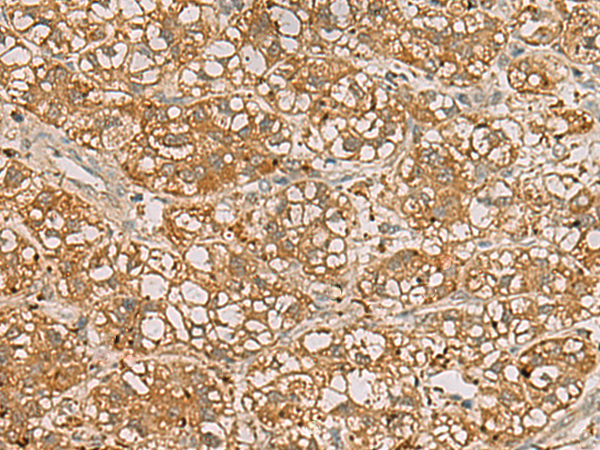

分类: 科研抗体货号: P02868别名: TPMTD应用: IHC反应种属: Human